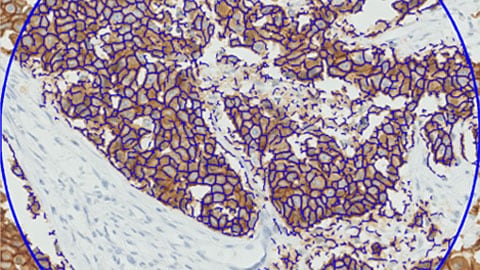

Digital pathology will open up new ways to get more information from tissue samples. The development of specific algorithms for automated interpretation of advanced stains will facilitate the objective analysis of images. By developing advanced algorithms and data management systems, we can help you translate the ‘Big Data’ promise into knowledge. This can be an important stepping-stone towards better health management and patient outcomes.

IntelliSite’s image analysis applications offer tools that provide exciting new insights for research pathologists. In addition to our advanced algorithms, the solution’s open platform has spawned the development of tools from several partners.